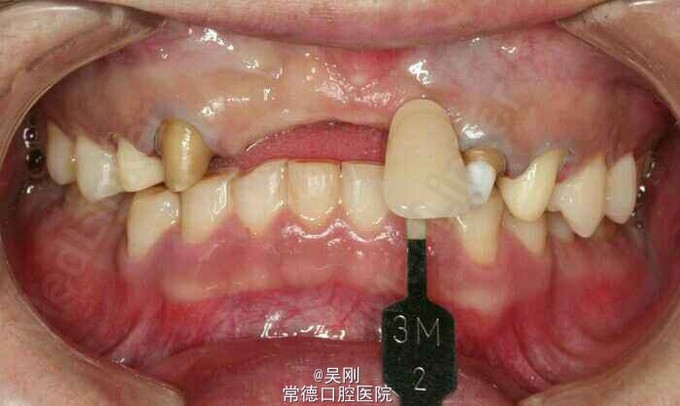

前牙缺失三天。 上颌前牙五年前因外伤导致脱了,在当地医院做固定修复,近三年来修复体反复折断(基牙折断)三次,并且每次制作增加基牙。

11、12、21缺失,牙槽骨(唇侧更明显)吸收严重成月牙状。 22残根断面距龈上约1.5mm,13牙髓坏死。 深覆 牙合 。 下前牙之间有间隙。 缺牙区距离太长,超过实际距离。 X线显示下前牙与上颌缺牙区牙槽嵴角度成反 牙合 。